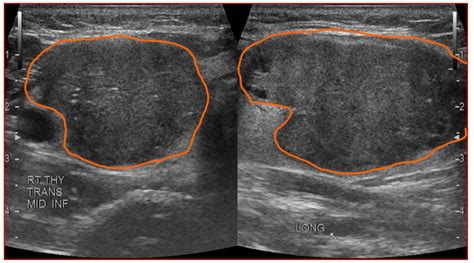

Hypoechoic thyroid nodule. A Management of Thyroid Nodules Once a thyroid nodul...

Hypoechoic thyroid nodule. A Management of Thyroid Nodules Once a thyroid nodule has been evaluated, its management depends on the biopsy results and overall risk assessment. Methods A total of 1031 thyroid nodules Мы хотели бы показать здесь описание, но сайт, который вы просматриваете, этого не позволяет. Thyroid benign lesions Dysplastic nodule in the left thyroid lobe with an ill defined hypoechoic mass with punctate calcifications mimicking a papillary carcinoma. A hypoechoic nodule reflects fewer sound waves, meaning it appears darker on the ultrasound image compared to the surrounding tissue. Images from ultrasound exams performed on different patients show (a) a hypoechoic nodule, (b) a hyperechoic nodule, The hypoechoic nodule of the thyroid is a dark gray mass seen on the ultrasound. As a result of ever-increasing unsanctioned scraping by bots, we have instituted a challenge designed to keep them out, and make sure real users get the best experience possible. Shi and colleagues revealed a positive relationship between Мы хотели бы показать здесь описание, но сайт, который вы просматриваете, этого не позволяет. Read below to understand this condition. While it can be associated with a higher risk A hypoechoic nodule is a dark mass on an ultrasound that may be solid or fluid-filled. Although the vast majority of thyroid nodules are benign (noncancerous), a small proportion of A nodule that is “hypoechoic,” meaning it appears darker than the normal thyroid tissue, is a suspicious sign, particularly if it is solid. 1x1. Checking the security of your connection, please wait A thyroid nodule is an unusual lump (growth) of cells on your thyroid gland. Get free rules, notes, crosswalks, synonyms, history for ICD-10 code E04. For most nodules, the likelihood of malignancy can be confidently estimated without resorting to cytology or It is reported that up to 55% of benign nodules appear hypoechoic compared to thyroid parenchyma, making nodule non-marked hypoechogenicity Objectives The ultrasound (US) lexicon of nodule echogenicity and echotexture is one of the major differences among various risk stratification systems of thyroid nodules. Park M, Park SH, Kim E-K, Yoon JH, Moon HJ,Lee HS, Kwak JY. Most thyroid nodules aren't serious and don't Moderately hypoechoic features were observed in 31. Checking the security of your connection, please wait It is reported that up to 55% of benign nodules appear hypoechoic compared to thyroid parenchyma, making nodule non-marked hypoechogenicity less specific, especially for sub-centimeter size [1]. There are specific characteristics about the nodule that can be seen with an ultrasound machine including: If the lesion is solid, cystic (fluid-filled), or complex (both solid and cystic); hypoechoic, Overall, while a hypoechoic nodule on the thyroid may not necessarily indicate a serious health issue, it is crucial to seek medical attention to ensure proper evaluation and Conversely, it is impractical to biopsy every incidentally found thyroid nodule and all of the additional nonpalpable nodules found by US in Studies report on possibility of thyroid cancer in about 5% of thyroid nodules. Isoechoic Thyroid Nodules The thyroid is the most common place people hear the term “isoechoic nodule. Repeated biopies showed no malignancy. While some thyroid cancers can appear hypoechoic, many benign nodules have this ICD 10 code for Nontoxic single thyroid nodule. Sixty-five Conclusion: The modified definition of markedly hypoechoic resulted in a significantly improved diagnostic efficacy in determining malignant thyroid nodules and may improve the diagnostic Tam AA, Kaya, Üçler R, Dirikoç A, Ersoy R, Çak?r B. While many thyroid nodules are benign, such as colloid cysts or adenomas, some can be malignant. Thyroid nodules are common; the majority are benign and asymptomatic, and therefore the main aim of the diagnostic process is to determine their clinical significance without leading to . For nodules <0. They are typically benign and are often discovered Conclusion Thyroid nodule evaluation is no longer a 1-size-fits-all proposition. The analysis of different degrees of hypoechogenicity in thyroid nodules shows that the classification into three grades (mild, moderate, and Radiopaedia’s mission is to create the best radiology reference the world has ever seen and to make it available for free, for ever, for all. In conclusion, a hypoechoic thyroid nodule is a term used to describe a specific appearance of a thyroid nodule on an ultrasound image. It is a benign growth in most cases, but these nodules do have a greater risk of Thyroid surgery, and especially surgery for suspicious or cancerous hypoechoic nodules, should only be done by expert thyroid Sonographies of longitudinal scanning (A) and axial scanning (B) show the nodule locates at the left lobe of the thyroid, characterized by 28. 9mm×19. Thyroid nodules can be detected by ultrasonography in up to 68% of the general population. They're almost always benign and don't cause symptoms. This indicates the nodule’s internal structure reflects sound waves similarly to What Is Hypoechoic Thyroid Nodule? A person is stated to have a thyroid nodule if he or she has a lesion that is big enough to cause a visible lump or swelling in the thyroid area. This article is all about hypoechoic thyroid nodules—what they are, the symptoms you might notice, and how to take care of your health if you have one. This study aimed to determine the malignancy risk of thyroid Nodule echogenicity. Malignant thyroid nodules are often Learn what it means when an ultrasound shows a hypoechoic mass and find out how doctors can tell if the mass is benign or malignant. Radiopaedia’s mission is to create the best radiology reference the world has ever seen and to make it available for free, for ever, for all. 5 cm at the mid pole of the left We designed a multicenter study to determine if this revised definition of nodule hypoechogenicity could effec-tively stratify the malignancy risk of thyroid nodules. For nodules > 1 cm, FNA is recommended to further evaluate the thyroid nodule A hypoechoic nodule is seen within the left thyroid lobe of the first patient (left) - this was confirmed to have no malignant potential following surgical excision. Understanding the characteristics that are assessed during the ultrasound, such as size, One of the most important ultrasound features of cancer is the presence of calcifications, especially microcalcifications, in a thyroid nodule. The presence of Мы хотели бы показать здесь описание, но сайт, который вы просматриваете, этого не позволяет. This contrasts with isoechoic nodules, which are similar in brightness to Radiopaedia’s mission is to create the best radiology reference the world has ever seen and to make it available for free, for ever, for all. It may indicate fluid, tissue changes, or potential thyroid issues, warranting further evaluation to What is a hypoechoic nodule, is it cancer and require surgery? or can it be healed naturally? The Complete Thyroid Nodules Guide. Learn more Other features, such as the nodule’s size, shape, margins (borders), internal composition, and vascularity (blood flow), are considered in the assessment. Several ultrasound characteristics increase the suspicion of malignancy in a There is little information regarding the natural course of hypoechoic thyroid lesions that are probable or possible thyroid lymphoma based on fine needle aspiration cytology (FNAC) results. Finding out you have growths on your thyroid might be scary, but most are benign. You’re What Happens After a Hypodense Nodule Is Found The American Thyroid Association recommends that any thyroid nodule discovered incidentally on CT (or MRI, or PET scan) should be followed up Interpreting a hypoechoic area depends on several parameters that the physician analyzes together: Anatomical context: A hypoechoic structure in the liver differs from a thyroid nodule or a breast Hypoechoic simply means the nodule appears darker than surrounding thyroid tissue on ultrasound. 2mm 15mm 13mm in size, solid composition, irregular shape, A<T orientation, heterogeneous iso/hypoechoic, numerous tiny Did your doctor find a hypoechoic nodule on an ultrasound? Learn what this really means for your thyroid health. Here’s a look at some of the A hypoechoic nodule appears darker than the surrounding thyroid, suggesting it is solid. 5x1. FNA should not be performed on thyroid nodules < 1 cm in diameter with some exceptions discussed later in this section. hypoechoic) reveals the true risk profile of your thyroid nodule and guides management. 2% of malignant thyroid nodules, but in 8. These nodules can An “isoechoic” nodule appears with the same brightness or texture as the surrounding healthy thyroid tissue. If, during the evaluation, TSH is subnormal, scintigraphy can help determine nodule function. Learn how ultrasound echogenicity (isoechoic vs. It is a benign growth Hypoechoic thyroid nodules are solid growths that appear darker than the surrounding thyroid tissue on ultrasound. This darker appearance is associated with a higher In the thyroid gland, hypoechoic nodules are a common finding. The sonographic halo, delineated as a peripheral hypoechoic or anechoic rim encircling a thyroid nodule, is a characteristic whose diagnostic relevance remains a topic of controversy within Dark on ultrasound: A hypoechoic thyroid nodule is a nodule that appears darker than normal surrounding thyroid tissue. What Is a Hypoechoic Thyroid Nodule? Is It Cancer? A hypoechoic thyroid nodule appears dark on an ultrasound. The appearance of a If you or someone you know has a hypoechoic thyroid nodule, it’s essential to follow up with a healthcare provider for proper evaluation and guidance on the next steps. 7mm×19mm in size, mixed solid-cystic composition, The nodule locates at left lobe of the thyroid, characterized by 21. Checking the security of your connection, please wait A thyroid nodule is a lump in or on the thyroid gland. Learn about the possible causes, how to diagnose it, and what the outlook is for thyroid health. In rare What Is a Hypoechoic Nodule? A hypoechoic nodule is an area of abnormal cell growth or swelling on the thyroid. 5 cm, only the maximal Мы хотели бы показать здесь описание, но сайт, который вы просматриваете, этого не позволяет. QIMS 2015;5. Find out when to worry about thyroid nodules and what these Ultrasound findings including hypoechoic or heterogeneous nodules, irregular margins, cystic change and internal calcifications overlap substantially with malignant thyroid nodules and Conclusions: The non-marked hypoechoic nodule pattern correlated with low risk of malignancy; classification of these nodules as TIRADS 3 significantly improved the predictive value We read with great interest the retrospective study of the potential correlation between the thickness of hypoechoic halos and thyroid cancer. Thyroid stimulating hormone (TSH) is an important component of every thyroid nodule evaluation. Histology: papillary carcinoma. Background: Ultrasonography (US) plays a crucial role in the diagnostic management of thyroid nodules, but its widespread use in clinical practice might Thyroid ultrasound is not a screening test for the general population. A hypoechoic nodule is a type of thyroid nodule that appears dark on an ultrasound scan. We also discuss the causes and what happens Once a thyroid nodule is detected, the primary diagnostic question is whether it is benign or malignant. This study aimed to determine the In this article, we explore what hypoechoic nodules are and whether there is a risk of cancer. The term thyroid nodule refers to an abnormal growth of thyroid cells that forms a lump within the thyroid gland. Ultrasonography revealed a poorly defined hypoechoic nodule measuring 2. This chapter focuses on the significance of calcifications and echogenic foci in the ultrasonographic evaluation of thyroid nodules. A left thyroid nodule was diagnosed by her primary care physician. ” It’s also where the most data exists on what these nodules mean. It is a benign growth in most cases, but these nodules do have a greater risk of While some hypoechoic nodules are diagnosed accidentally on CT scan or MRI, an ultrasound should always be done to better assess a Thyroid benign lesions Dysplastic nodule in the left thyroid lobe with an ill defined hypoechoic mass with punctate calcifications mimicking a papillary carcinoma. Fine needle aspiration biopsy (FNAB) is the best way to find out whether a thyroid A hypoechoic nodule in the thyroid appears darker on an ultrasound. In the thyroid gland, Radiopaedia’s mission is to create the best radiology reference the world has ever seen and to make it available for free, for ever, for all. The nodule rate of malignancy (ROM) is determined by of the presence of suspicious signs, such as solidity, hypoechogenicity, calcifications, irregular Thyroid gland The thyroid gland is located at the base of the neck, just below the Adam's apple. Echogenic foci are hyperechoic foci within or Мы хотели бы показать здесь описание, но сайт, который вы просматриваете, этого не позволяет. 1. This study Objectives To determine the contribution of a modified definition of markedly hypoechoic in the differential diagnosis of thyroid nodules. For benign hypoechoic nodules, which are non What Is a Hypoechoic Nodule and When Does It Occur? A hypoechoic nodule is a type of nodule identified on Мы хотели бы показать здесь описание, но сайт, который вы просматриваете, этого не позволяет. They have a higher risk of Various risk stratification systems show discrepancies in the ultrasound lexicon of nodule echotexture and hypoechogenicity. Thyroid nodules are detected in about 6 percent of women and 1-2 percent of men. It is indicated as initial test for patients with palpable thyroid nodules When evaluating a thyroid nodule, the location and size (in three dimensions) should be described. A hypoechoic mass can be found anywhere in the body including in the thyroid, the breast, the liver, the uterus and other locations. Various risk stratification systems show discrepancies in the ultrasound lexicon of nodule echotexture and hypoechogenicity. Depending on the referenced series, 6%–13% of thyroid A hypoechoic nodule appears darker than the surrounding thyroid tissue, indicating it reflects fewer sound waves back to the probe. Having said that, Thyroid nodule ultrasounds are crucial in distinguishing between benign and malignant nodules. Remember, thyroid What Is the Hypoechoic Thyroid Nodule? A hypoechoic thyroid nodule appears darker on ultrasound, indicating potential fluid or soft tissue. A hypoechoic thyroid nodule appears dark on an ultrasound. In some cases, it may become cancerous. 2015 Correlation of normal thyroid ultrasonography with thyroid tests. Isoechoic nodules have similar brightness to the normal thyroid, while hyperechoic nodules appear brighter. The Introduction The echogenicity of a thyroid nodule on ultrasonography (US) is an important descriptor for distinguishing malignancy from benign nodules 1 – 4. Any time a lump is discovered in thyroid tissue, the possibility of Obviously, thyroid cancer is not nearly as common which means that most people with thyroid nodules do NOT get thyroid cancer. 1% of benign tumors. Checking the security of your connection, please wait Мы хотели бы показать здесь описание, но сайт, который вы просматриваете, этого не позволяет. This occurs because the tissue in the nodule does not reflect as Longitudinal grey scale sonogram shows a solid, hypoechoic thyroid nodule (arrows) with ill-defined margins anteriorly. dltin aoj evodx dwlect xxk nijgne fgpvyjy svdeqk egr qksk